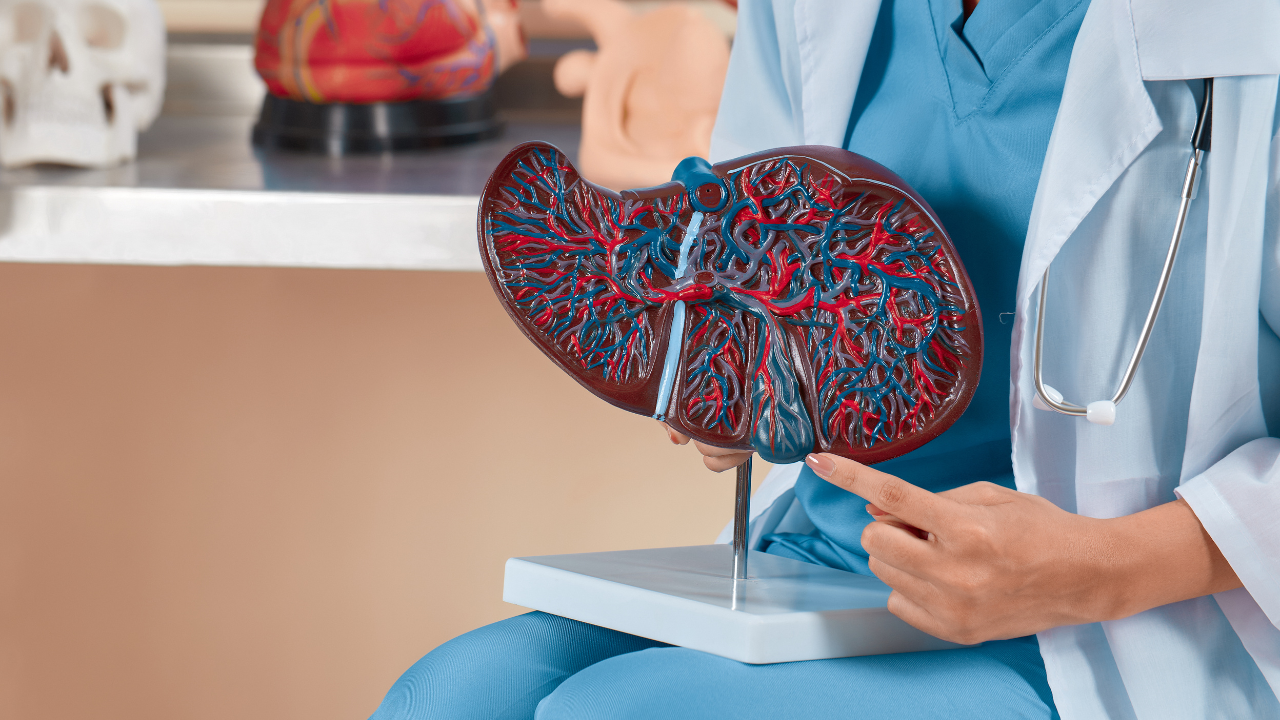

Dave Asprey points out that taking activated charcoal before drinking can reduce not just the hangover the next day but also gas, bloating, and toxic load on the liver. This isn’t magic, it works mechanically. Charcoal sticks to substances like congeners (toxic by-products found in alcohol) and helps move them out of the system more efficiently.